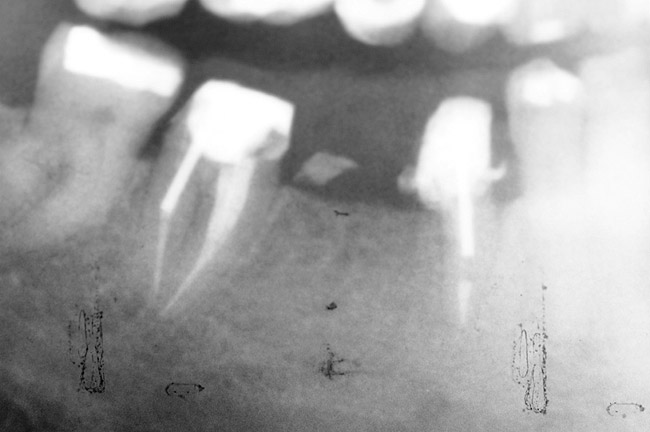

Figure 2  Same case as in Figure 1 after 1.5 years with no treatment. At that time, the bone loss affected the adjacent teeth. The apical extent of the bone loss was approximately 5 mm from the sinus floor.

Figure 2

Figure 3   Radiographic appearance of the repaired osseous defect seen in Figure 2 approximately 6 months after extraction and immediate bone grafting of the socket. Note the radiographic repair of the bone on teeth Nos. 4 and 6.

Figure 3